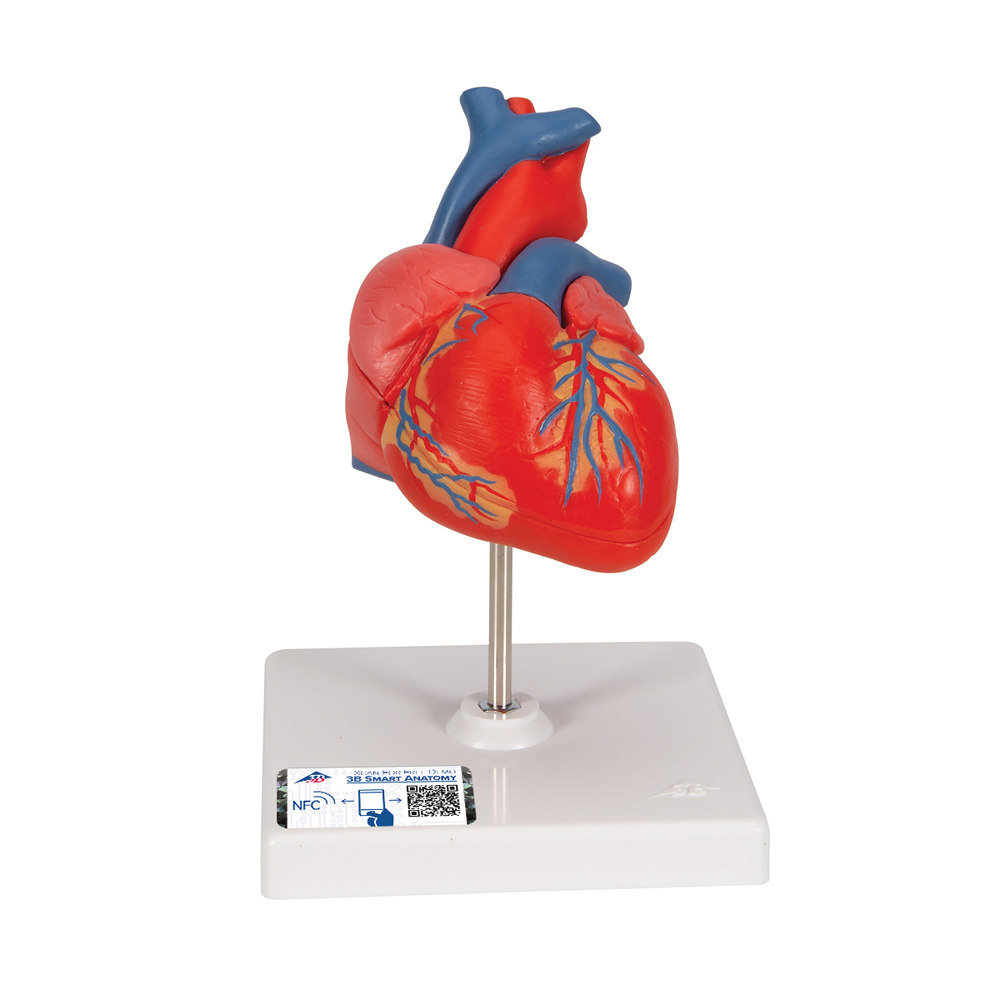

Фотографии и 3D-модели анатомии сердца человека